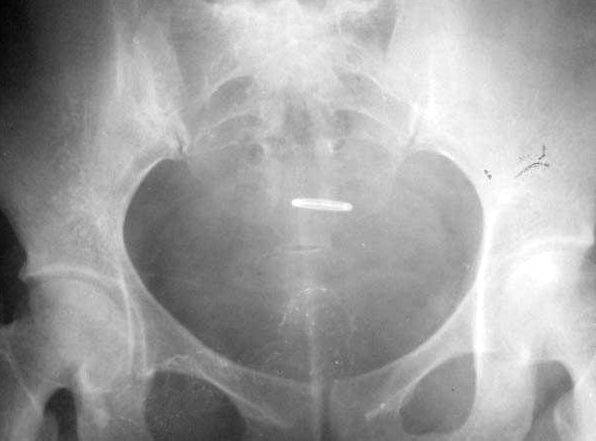

照片名称:膀胱癌

照片名称:膀胱癌2

照片名称:膀胱癌4

照片名称:膀胱癌5